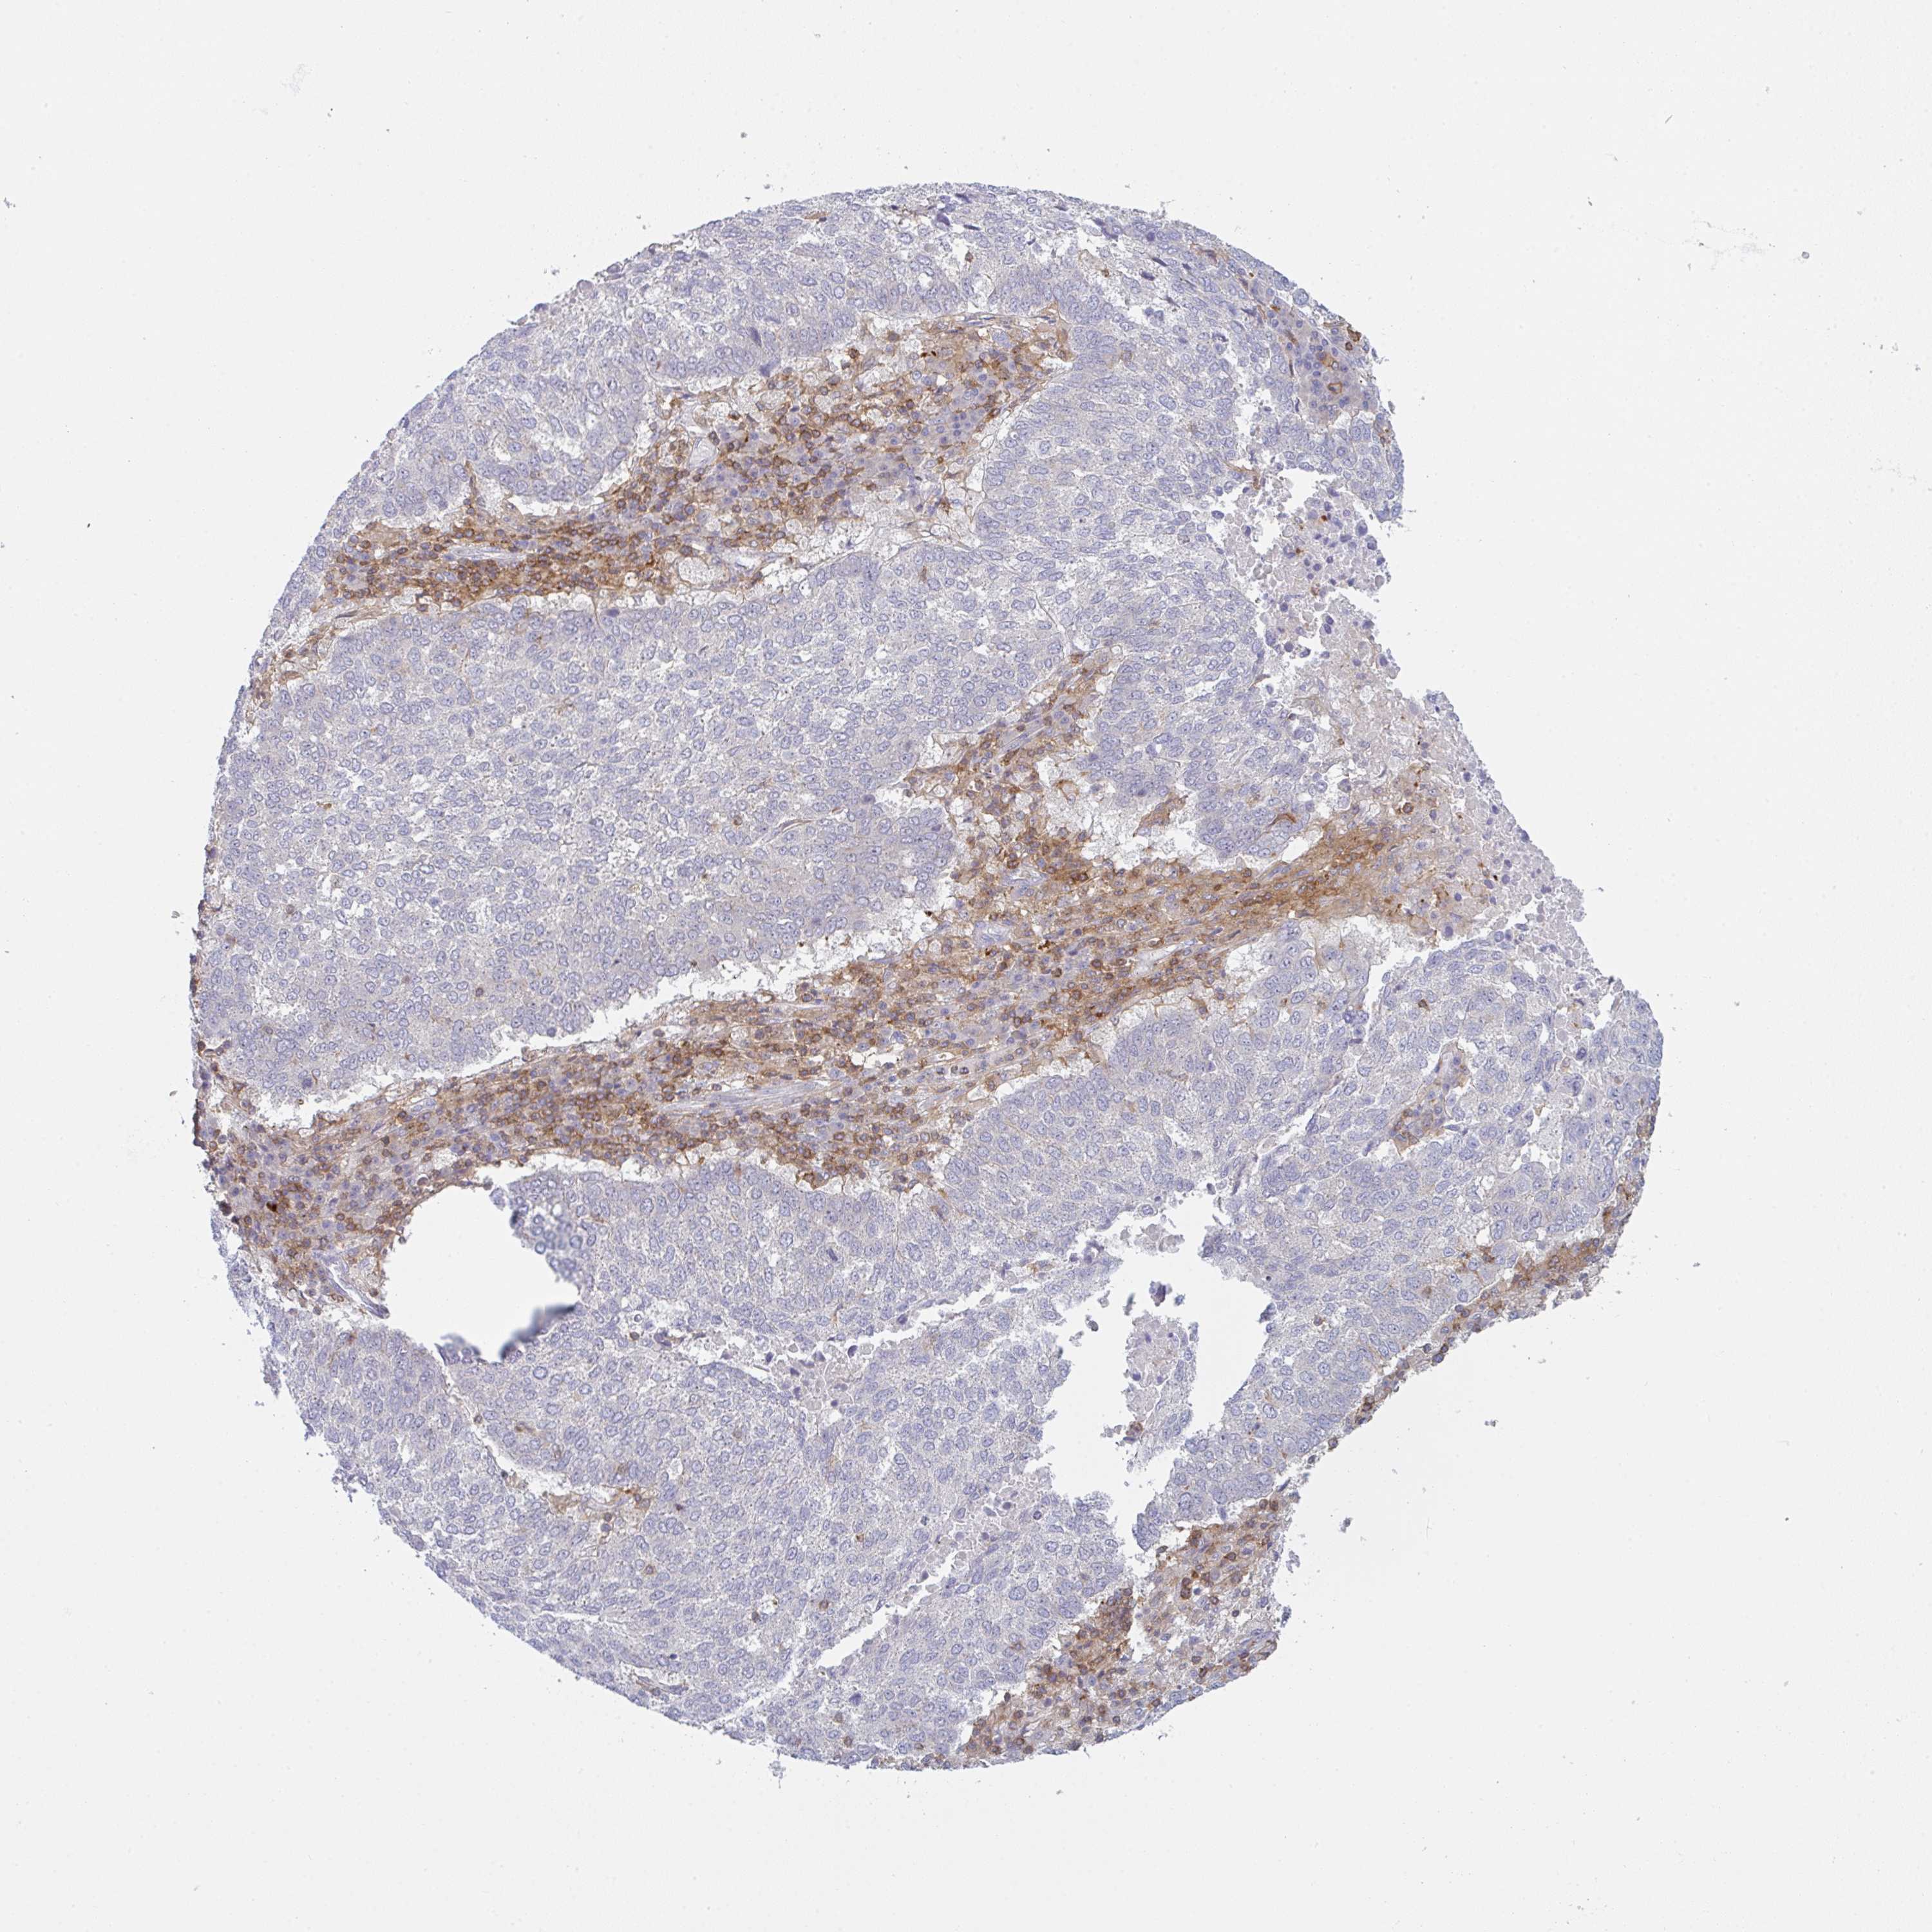

LUNG ADENOCARCINOMA (VALIDATION) - Interactive survival scatter ploti

The Survival Scatter plot shows the clinical status (i.e. dead or alive) for all individuals in the patient cohort, based on the same data that underlies the corresponding Kaplan-Meier plots. Patients that are alive at last time for follow-up are shown in blue and patients who have died during the study are shown in red.

The x-axis shows the expression levels (FPKM) of the investigated gene in the tumor tissue at the time of diagnosis. The y-axis shows the follow-up time after diagnosis (years). Both axes are complimented with kernel density curves demonstrating the data density over the axes. The top density plot shows the expression levels (FPKM) distribution among dead (red) and alive patients (blue). The right density plot shows the data density of the survived years of dead patients with high and low expression levels respectively, stratified using the cutoff indicated by the vertical dashed line through the Survival Scatter plot. This cutoff is automatically defined based on the FPKM cutoff that minimizes the p-score. The cutoff can be changed by dragging the vertical line or by entering a cutoff value in the square labeled "Current cut-off".

Under the Survival Scatter plot the p-score landscape (black curve; left axis) is shown together with dead median separation (red curve; right axis). Dead median separation is the difference in median mRNA expression between patients who have died with high and low expression, respectively. It is calculated as follows: median FPKM expression of dead patients with high expression - median FPKM expression of dead patients with low expression. This is intended to aid the user in visually exploring custom cutoffs and the associated p-scores and dead median separation.

Individual patient data is displayed and can be filtered by clicking on one or more of the category buttons on the top of the page. Categories describing expression level and patient information include: high, low, alive, dead, female, male and tumor stages. The scale of the x-axis can be toggled between linear and log-scale by clicking on the "x log" button. Mouse-over function shows TCGA ID, patient information and mRNA expression (FPKM) for each patient.

& Survival analysisi

Kaplan-Meier plots summarize results from analysis of correlation between mRNA expression level and patient survival. Patients were divided based on level of expression into one of the two groups "low" (under cut off) or "high" (over cut off). X-axis shows time for survival (years) and y-axis shows the probability of survival, where 1.0 corresponds to 100 percent.

CD80 is not prognostic in Lung Adenocarcinoma (validation)

Best expression cut offi

Based on the FPKM value of each gene, patients were classified into two groups and association between prognosis (survival) and gene expression (FPKM) was examined. The best expression cut-off refers the FPKM value that yields maximal difference with regard to survival between the two groups at the lowest log-rank P-value. Best expression cut-off was selected based on survival analysis .

When clicking on this number, the vertical dashed line indicating cut-off, the interactive survival plot, and the Kaplan-Meier curve will be adjusted to show results based on the best expression cut-off.

: 3.56

Median expressioni

Median expression refers to the median FPKM value calculated based on the gene expression (FPKM) data from all patients in this dataset. When clicking on this number, the vertical dashed line indicating cut-off, the interactive survival plot, and the Kaplan-Meier curve will be adjusted to show results based on the median expression.

: N/A

Median follow up timei

Median follow up time refers to the median time (years) after diagnosis with this type of cancer, based on clinical data from all patients in this dataset.

P scorei

Log-rank P value for Kaplan-Meier plot showing results from analysis of correlation between mRNA expression level and patient survival.

N/A

5-year survival highi

5-year survival for patients with higher expression than the expression cutoff.

For melanoma and glioma, 3-year survival is shown.

5-year survival lowi

5-year survival for patients with lower expression than the expression cutoff.

TCGA RNA samplesi

RNA-seq data is reported as average FPKM (number Fragments Per Kilobase of exon per Million reads), generated by the The Cancer Genome Atlas (TCGA) .

Normal distribution across the dataset is visualized with box plots, shown as median and 25th and 75th percentiles. Points are displayed as outliers if they are above or below 1.5 times the interquartile range. FPKM values of the individual samples are presented next to the box plot.

Average pTPM 5.3

Number of samples 105